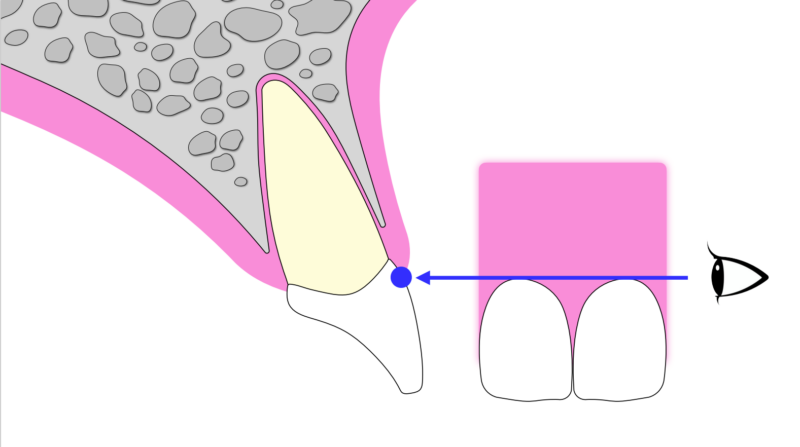

一般的に歯を抜いた後、そのまま放置すると骨や歯肉は時間とともに痩せてしまいます。(資料2〜5)

特に前歯ではこの影響が大きく、後からインプラントを入れる場合、骨を増やす処置(GBR)が必要になることも多く、治療回数や負担が増える傾向があります。

そこで近年注目されているのが、「抜歯と同時にインプラントを入れる方法」です。さらに、歯の一部をあえて残すことで歯肉や骨の形を維持する「ソケットシールドテクニック(SST)」という手法もあります。これにより、組織の吸収を最小限に抑え、より自然な仕上がりが期待できます。